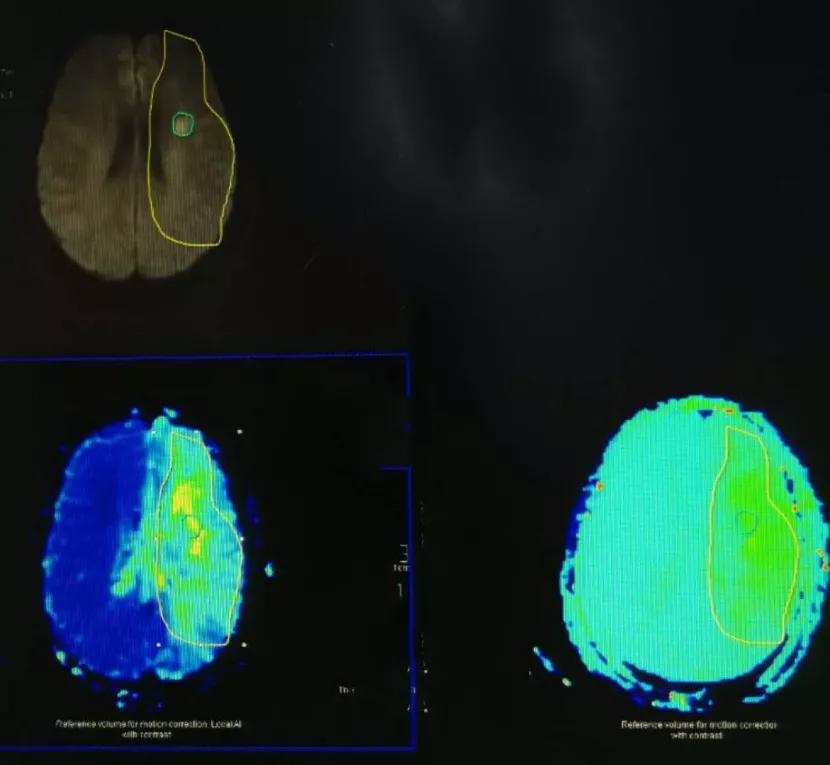

患者做头颈部血管CT(CTA)、数字减影全脑血管造影(DSA)检查,确认颅内动脉是否存在重度狭窄;一般需要完善磁共振(MRI)或CT灌注成像(CTP),必要时进行高分辨核磁共振检查。这些检查结果都要由神经内科医生结合临床进行评估。

术前核磁共振检查:左侧大脑半球梗死,左侧大脑中动脉供血区低血流灌注